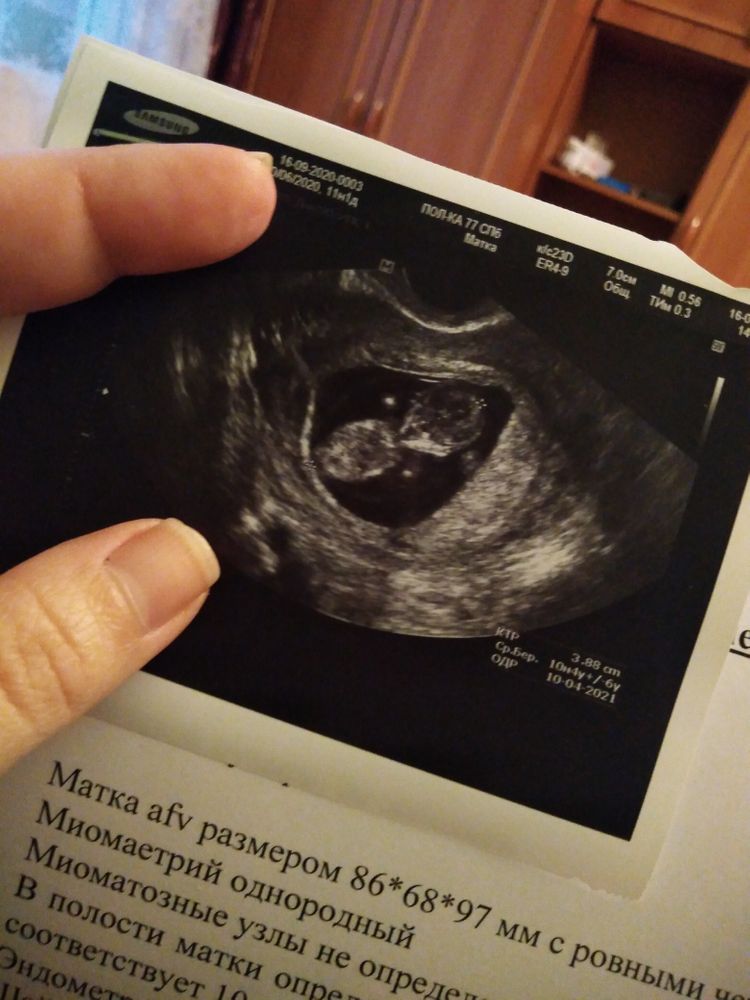

УЗИ, КТГ, доплерДоброго времени суток.Скажите пожалуйста у меня 10 недель, а на УЗИ есть плод размером с мандарин, но почему нету ручек и ножек, просто два пузыря... Или я просто накручиваю себя🤔🤔🤔

Ахах) Я тоже так сходила в 10 недель на неудачное узи. В чате все девочки выкладывали классные снимки со своими креветочками (как они их называли), там видно было и ручки и ножки. А мне дали смазанный снимок и там вообще ничего непонятно! Я пишу, почему у всех креветочки, а у меня колобок какой-то?) Но видимо вертелся, не хотел сниматься. Даже на экране ничего непонятно было плюс ещё и тонус сжал пя.

Вот что это? Яйцо в яйце, блин! Вышла расстроенная, думаю зачем столько денег отдала. Не могла даже срок высчитать долго🤦♀️

У вас тут как раз все понятно. Малышок лежит на спине прям лицом к вам. Даже немного видно ручки)

о, да у вас тут все видно))) пхх. точечки белые - это ножки и ручки были на вас направлены, поперечный срез. это голова и туловище) только мне кажется что голова слева. но я по узи вообще ламер, тут девочки на таком сроке даже пол умеют определять))))

Ребенок скорее всего лежал спиной к вам) потому только голова и туловище видны)))